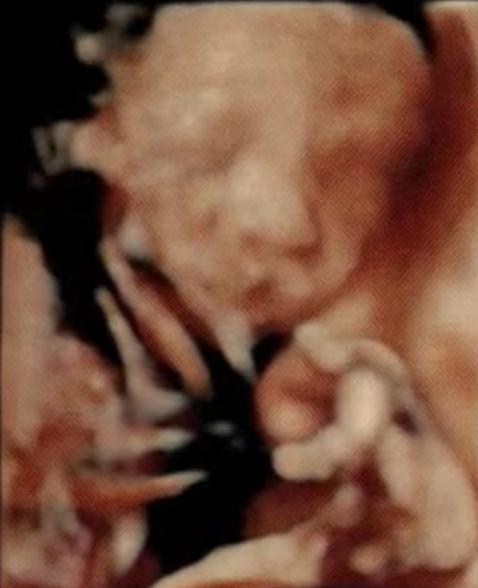

27週の妊婦です。先日病院でいただいた4dエコーの動画(5秒くらいのもの)を見ていて、赤ちゃんの口が割れているように見えて心配しています。口唇裂などの病気の可能性はありますか?

画像ですが、同じ5秒の中で、口を動かしていたのでそのうちの2枚を切り取って添付させていただきます。

医師からは特に何も言われず、「4dエコーはそういうもんだよ!」と言われてしまいましたが、上の子の時はそのように映っていたことがなかった為、不安で仕方ありません。

4Dエコーで、お口が割れているように見えるということでご相談ですね。

動いている時の様子を途中で写真として収めているものになります。

なので赤ちゃんがお口を動かしていることもありましたら、その時の写し方によってはお口が割れているように写ってしまうこともあるように思います。

口唇口蓋裂は、普通のエコーでも確認ができることもあります。

これまでのエコーでも特に先生からご指摘をされることがなかったようでしたら、その可能性は低いのではないかなと思いました。